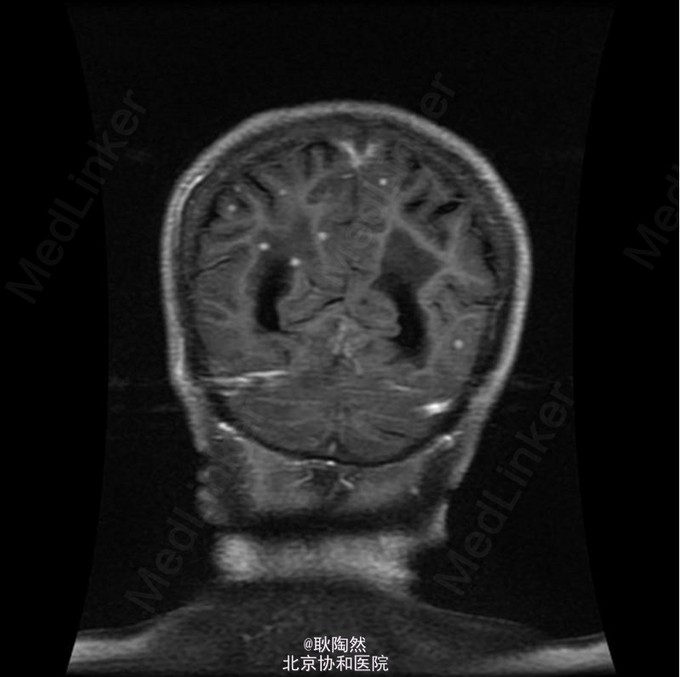

患者75岁老年女性,因“间断发热1年余,乏力、少语2周”于2014-12-25入院治疗。 2013年起患者无明显诱因出现发热,每日午后温度渐高,Tmax39℃,次日凌晨可降至正常。伴乏力,无盗汗、畏寒寒战、咳嗽咳痰等表现。外院胸部CT提示“肺部感染”,予莫西沙星治疗后体温正常。 2013-3患者出现T12椎体骨折,行手术治疗,术前有发热表现,予莫西沙星抗感染治疗后体温正常。2014-5因再次出现腰痛复诊,因前次手术窦道(左髂)迟迟未愈合,于左髂处取活检:坏死性肉芽肿,伴死骨形成,可见多核巨细胞及类上皮细胞,抗酸染色(-),不除外结核。 后患者间断发热。2014-8胸部CT示:右上肺尖后段、右中叶外侧段、左下肺外侧段散在片絮、云雾状不规则高密度灶,密度不均,提示感染;纵膈内未见肿大淋巴结。右肺病灶行肺穿活检:可见肺组织及部分横纹肌组织,肺组织变性坏死,周围小灶肉芽肿形成,纤维组织增生,慢性炎症细胞浸润,部分细胞增生。抗酸(-),PAS(-),六胺银(-)。 2014-12起患者出现神情淡漠,懒言少语,乏力加重,不能坐起或下床。遂入我科。 入我科后查PPD皮试:(+++);血T-SPOT.TB:MLC+IFN(A) 36SFC10^6MC,MLC+IFN(B) 704SFC10^6MC; 胸腹盆CT(平扫):右肺上叶后段胸膜下肿块大致同前;两上肺及右中肺粟粒样结节并两肺多发斑片索条及散在钙化灶,考虑结核性病变;两肺门多发钙化灶,纵隔多发淋巴结;双侧胸膜增厚,大致同前;胸8-腰4 椎体多发内固定器,部分椎体骨质破坏,可为椎体结核术后改变;胸11-腰3 椎体左旁多发低密度影并环形强化,考虑椎旁脓肿;骶骨前方、直肠后方片状低密度影,渗出性改变不除外。 行腰穿:脑脊液压力为88mmH2O。脑脊液常规:外观 无色透明,细胞总数 12*10^6/L,白细胞总数 0*10^6/L,单核 0,多核 0;脑脊液生化:CSF-Pro 0.76g/L,CSF-Cl 115mmol/L,CSF-Glu 1.5mmol/L。脑脊液抗酸染色(-)、脑脊液结核、非结核分枝杆菌DNA(-);脑脊液T-SPOT.TB:MLC+IFN(A) 24 SFC10^6MC,MLC+IFN(B) 132 SFC10^6MC;脑脊液细胞学:结论:淋巴细胞性炎症,WBC 1000/0.5ml,AL 阳性(+),AM 阴性(-),PC 阴性(-),TC 阴性(-),RBC -,CL ++,LY% 90%,MONO% 5%,NEUT% 5.000%; 考虑患者为播散性结核感染,有肺、骨、中枢神经系统受累。予异烟肼、利福喷丁、乙胺丁醇、拜复乐四联抗结核治疗。